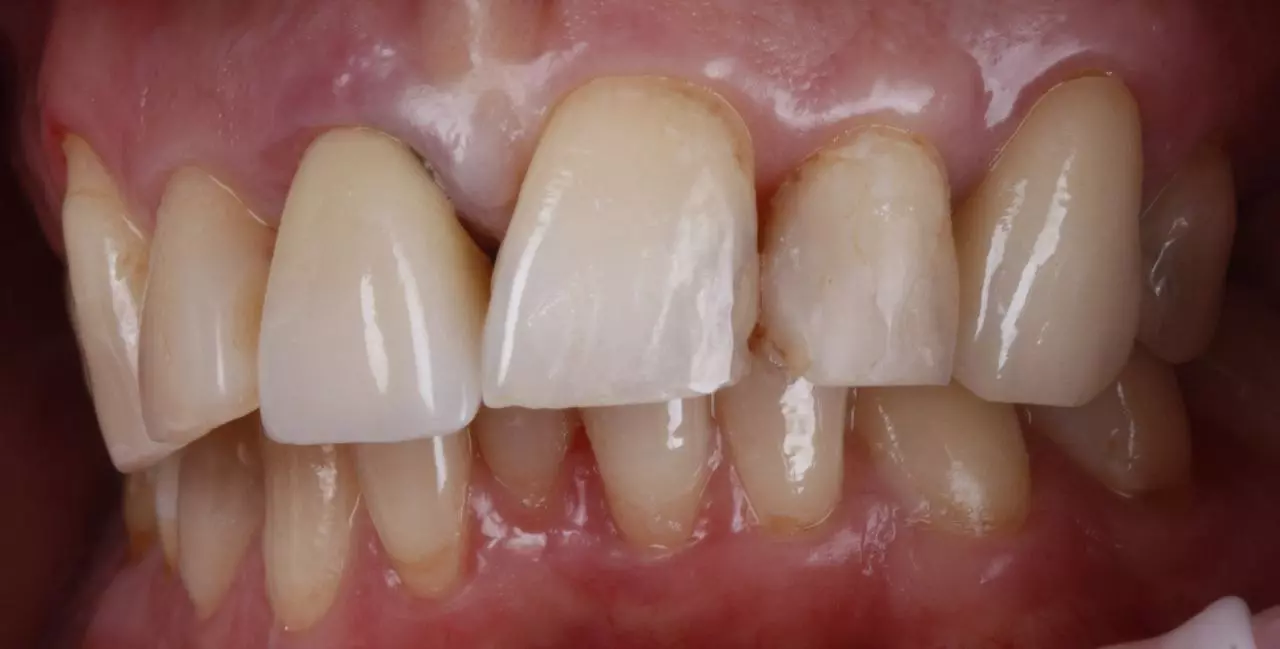

Художня реставрація 21.22.